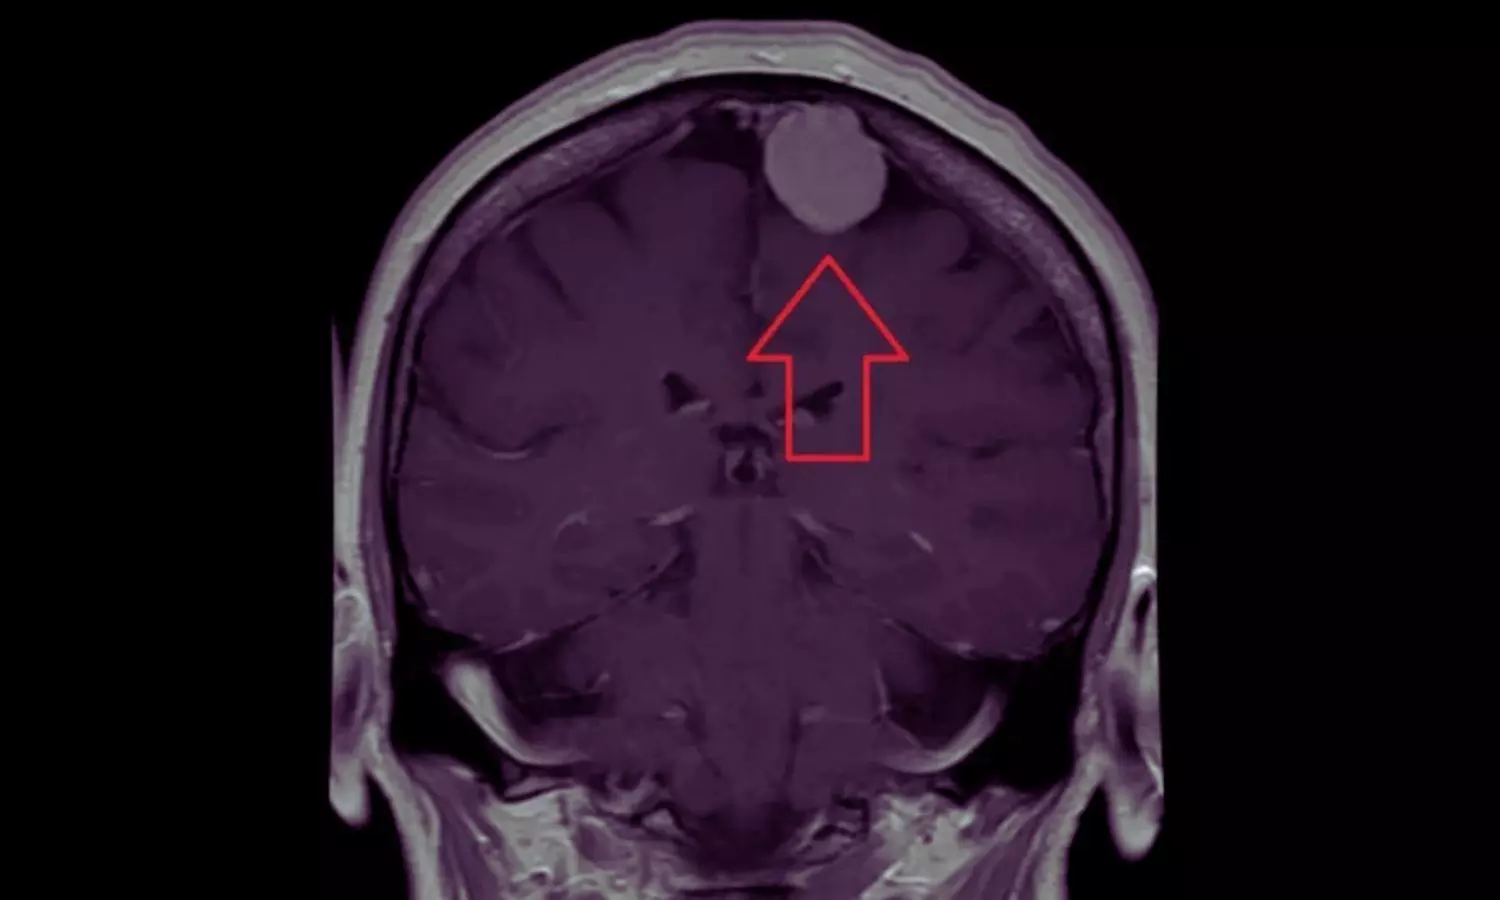

Depot Medroxyprogesterone Acetate Use Linked to Higher Meningioma Risk in Women: JAMA